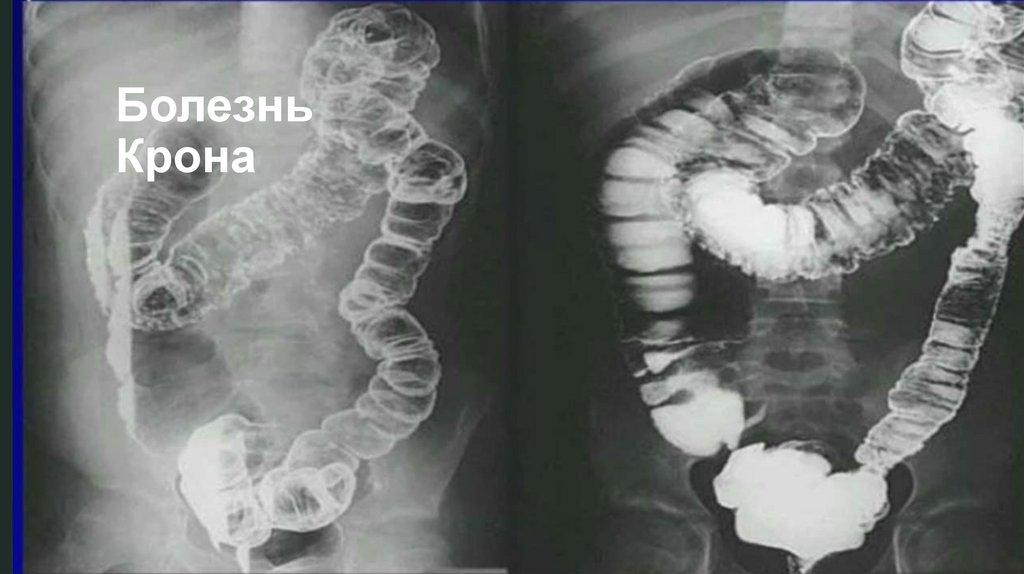

Диагностику болезни Крона осуществляют с помощью лабораторных

и функциональных исследований. Максимально информативные

методики – компьютерная томография и колоноскопия. На

томограмме можно обнаружить свищи и абсцессы, а колоноскопия

дает представление о состоянии слизистой (наличие воспаленных

участков, эрозий, изъязвлений стенки кишечника) и позволяет при

необходимости взять биопсию. Дополнительные методы

диагностики – рентгенография кишечника с бариевой смесью.

Можно получить снимки как тонкого, так и толстого кишечника –

контрастная бариевая смесь заполняет полость кишки и выявляет

сужения просвета и язвенные дефекты стенки, свищи.